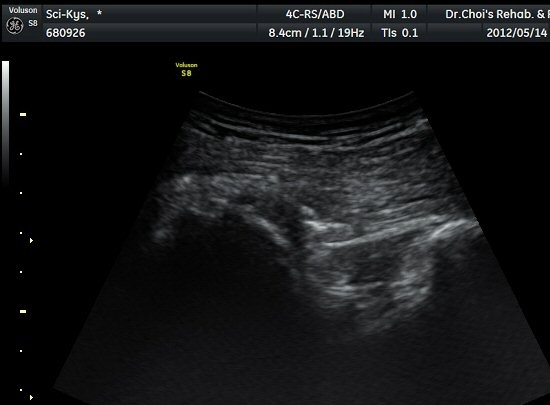

¾ûµ¢ÀÌ Á°ñ¿¡¼­ Á°ñ½Å°æ Ⱦ´Ü¸é°Ë»ç¿¡¼­ ´ëµÐ±Ù°ú quadratus femoris »çÀÌÀÇ ±Ù¸·

°æ°èºÎ¿¡¼­ Á°ñ½Å°æÀÌ °üÂûµÇ´Âµ¥ ³»Ãø Á°ñ°áÀý(ischial tuberosity) ÃøÀ¸·Î Ä¡¿ìÃÄ

ÀÖ´Â °ÍÀ¸·Î ÆÇ´ÜµÈ´Ù(±×¸² 1, 2, 3).

ŽÃËÀÚ¸¦ ¾à°£ ±ÙÀ§ºÎ·Î À̵¿ÇÏ´Ï °æ°è°¡ ºÒºÐ¸íÇÑ »À°¡ Á°ñ½Å°æ ¿ÜÃø¿¡¼­ µ¹ÃâÇϸ鼭

Á°ñ½Å°æÀ» ³»ÃøÀ¸·Î ½ÉÇÏ°Ô ÀüÀ§½ÃŲ´Ù(±×¸² 4, 5).